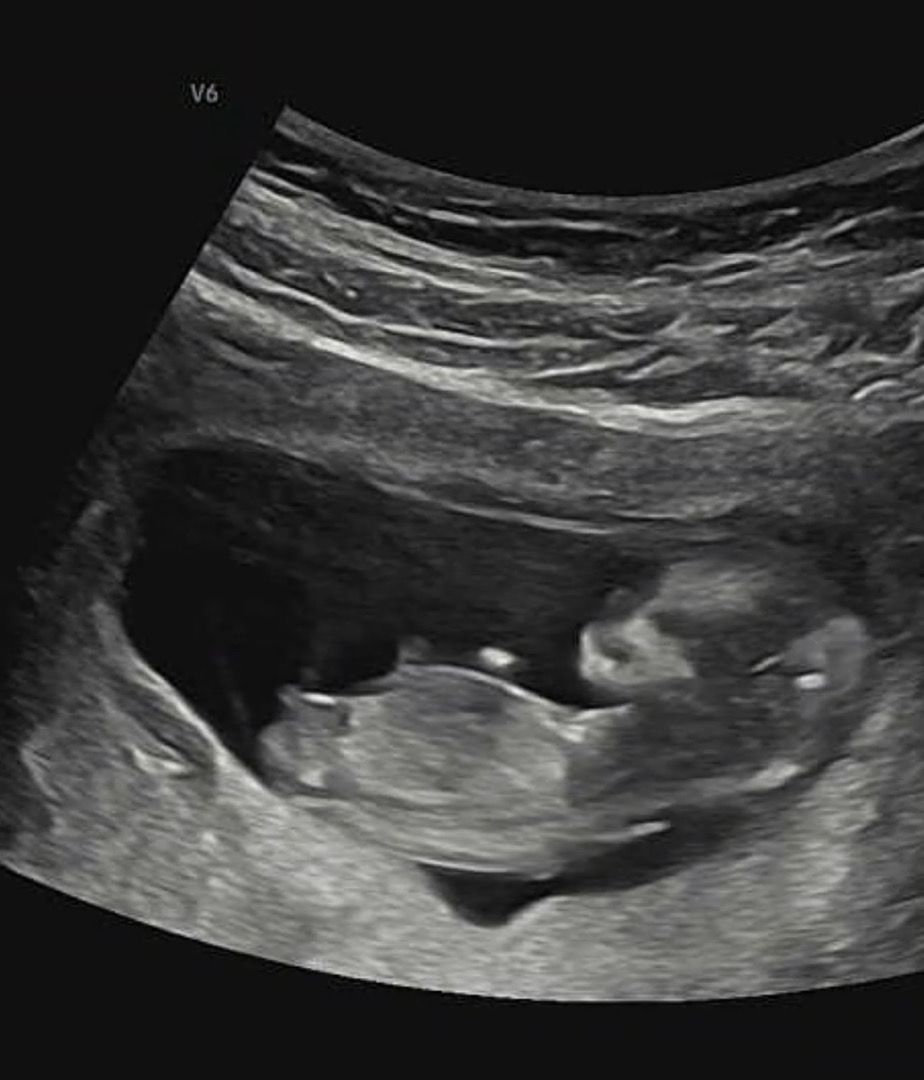

성별 각도법 봐주세요!

11주 6일이 초음파였어요 ㅎㅎ 혹시 보이시나요? 댓글에도 사진 하나 더 남겨둘게요..!

이건 확대된 상태여서 좀 잘렸지만 여기서도 생식선이 보이는 것 같아서요 ㅎㅎ 같이 봐주세요~!